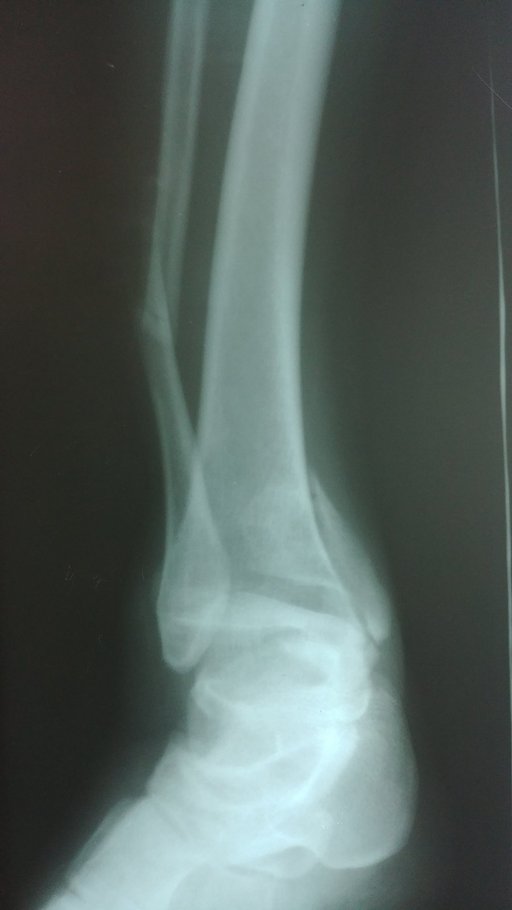

Хворий М. 39 р. звернувся в травмпункт КНП ТМКЛШД через 40хв після травми яку отримав в побуті при неправильному приземленні під час стрибку. Оглянутий травматологом травмпункту, направлена на рентгенографію. Згідно даних рентгенограм встановлено діагноз: Закритий перелом обох кісточок правої гомілки зі зміщенням уламків. Хворому накладено тимчасову фіксацію та направлено в приймальне відділення КНП ТМКЛШД. Повторно огляд. травматологом стаціонару. При огляді відмічається незначний набряк, біль, порушення функції н\кінцівки. Встановлено діагноз : Закритий перелом обох кісточок правої гомілки зі зміщенням.

Хворому рекомендовано оперативне втручання, на яке була отримана згода. При госпіталізації проведено необхідні інструментальні та лабораторні методи обстежень та огляд консультантами (терапевтом та анестезіологом). В екстреному порядку хворому проведено оперативне втручання – Відкрита репозиція з МОС перелому зовнішньої кісточки дистальною м\гомілковою пластиною LCP та відкрита репозиція з МОС внутрішньої кісточки гвинтами та антиковзною пластиною. Після оперативного втручання хворий переведений в палату. З 2-3 доби хворому дозволено активні рухи у г\ступневому суглобі без навантаження на праву н\кінцівку. Шви знято на 11 добу, хворий в задовільному стані з наданими рекомендаціями щодо тактики подальшого лікування виписана з травматологічного відділення на амбулаторне лікування